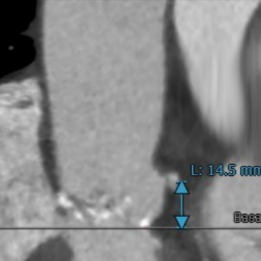

术前CT评估:

术前CT结果显示,患者主动脉瓣瓣环周长:82mm ,平均瓣环直径:26.1mm,左流出道平均直径27.0mm,瓦氏窦最小径32.5mm,窦管结合交界处(STJ)31.1mm,三叶瓣,中度钙化,钙化分布不均匀,主要位于无冠窦,瓣叶未见增生肥厚。左冠高度尚14.5,右冠高度9.9,可见右冠高度略低,结合瓣叶长度,瓣叶钙化分布等综合因素考虑,术中存在一定的冠脉遮挡风险。双侧入路血管直径尚可,无明显钙化,最小直径为8.9mm。

主动脉根部评估

冠脉阻挡风险评估及钙化程度分析